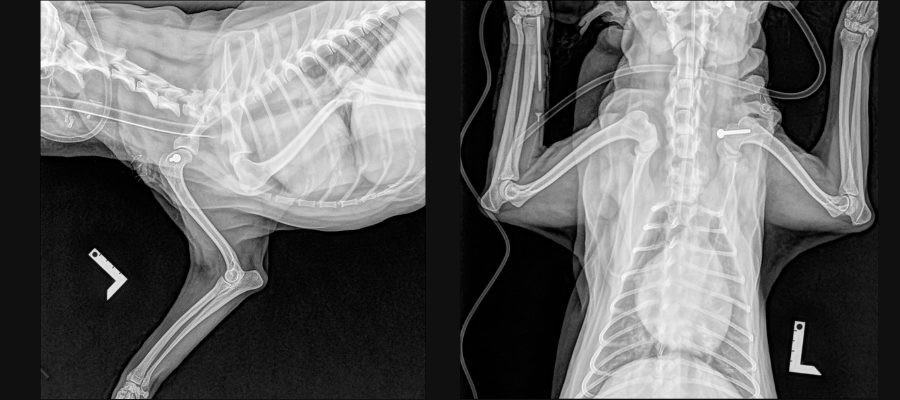

<術後のレントゲン>

脱臼を整復し、上腕二頭筋腱内側転移術により再脱臼を予防しています。

▼術前

▼術後